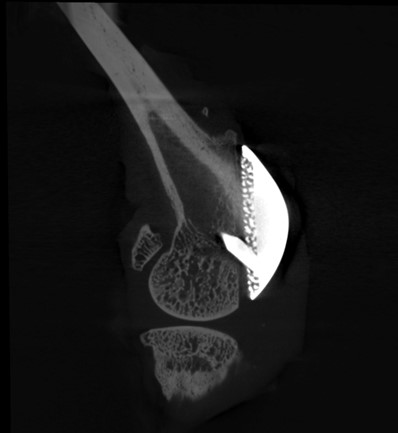

Micro-CT Imaging of Implant Osseointegration in Rabbit Models

High‑resolution micro-CT enables the non‑destructive, 3D visualization of implants and surrounding bone over time. The images presented here showcase the use of micro-CT to study periprosthetic joint implantation and osseointegration in rabbit models, allowing tracking of implant positioning, bone remodeling, and early indicators of bone integration at multiple time points.

Below are micro-CT reconstructions of a femoral implant in a rabbit knee model. High-resolution imaging enables tracking of implant position and progressive changes at the implant-bone interface over time.

medullary cavity